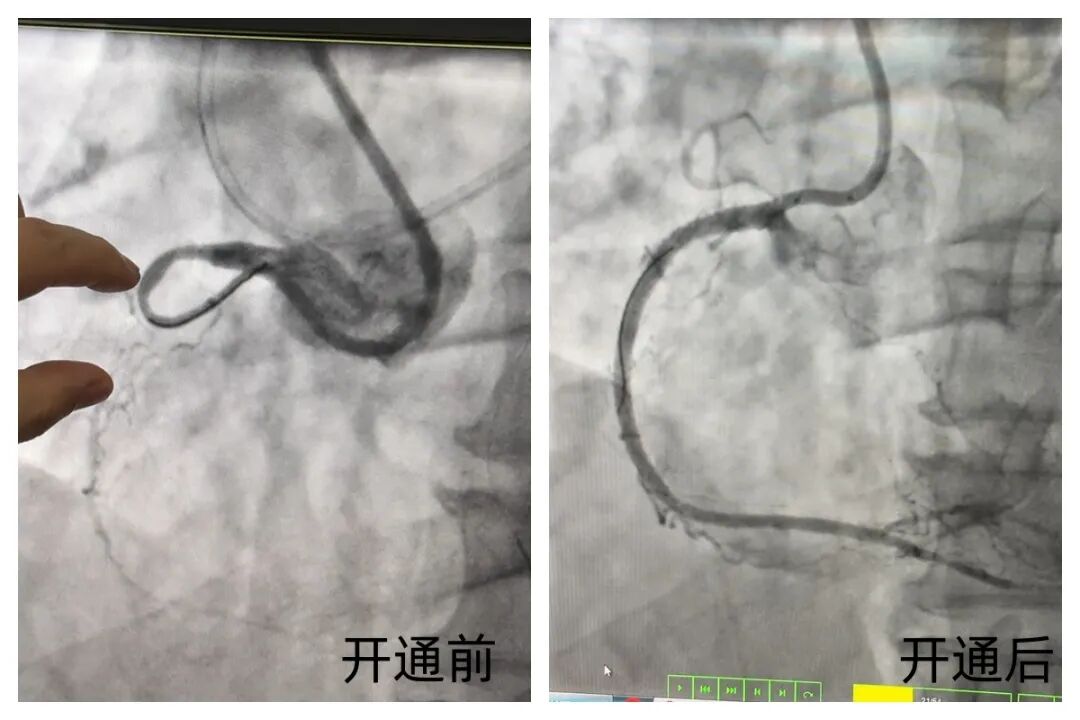

近日,这位饱受慢性冠脉闭塞顽疾困扰的中年男性患者迎来转机。阜外华中心血管病医院冠心病五病区闫瑞副主任、陈小贞副主任医师、方莉娜主治医师等专家,采用正向联合逆向介入技术,成功为其开通闭塞十年的右冠状动脉。

术中,面对闭塞时间长、组织纤维化严重的复杂病变,团队率先采用IVUS(血管内超声)指导下平行导丝技术进行正向尝试,在难以突破的情况下迅速启动逆向介入治疗,精准建立远端通道。

凭借娴熟的操作和默契配合,团队最终成功开通闭塞血管,原本纤细僵硬的血管恢复通畅,管径较术前明显增粗,心肌供血得到根本性改善。